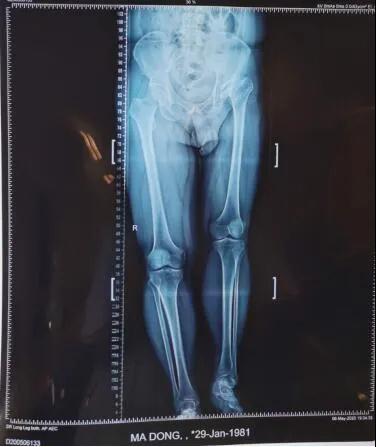

19日,beat365唯一官方网站第六附属医院骨病矫形外科主任李璐兵向记者透露:预计3个月后,有望像正常人一样自如行走。当日,记者在病房走廊看到,马先生手扶助行器,正在练习行走。“17日手术的,今儿就可以下地了。”马先生说。39岁的马先生,年幼时就患有左髋化脓性关节炎,因当时治疗条件有限,造成后期左髋关节骨质破坏严重,左下肢比右下肢短缩了6厘米,走路时跛行很明显,加上左髋关节因为骨质破坏严重导致活动范围受限,就连穿袜子都需要别人帮助。

从拍摄的影像片看出,马先生左侧股骨头已基本消失并且明显上移,错位明显,已与“假”的髋臼形成“假”关节。

整个手术进行了两个小时,将置换后的髋关节假体准确复位,为患者重建了髋关节并且矫正两条腿基本恢复等长。